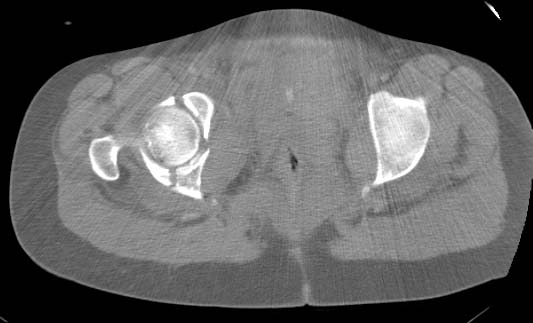

Pelvic CT - Click to Magnify